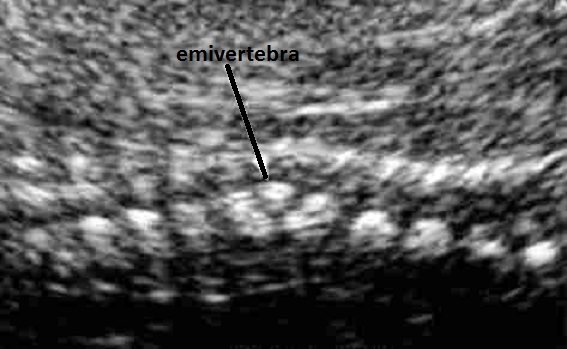

anomalie vertebrali (fusione, emivertebre, scoliosi)

V) anomalie Vertebrali (fusione, emivertebre, scoliosi),

1) scoliosi o emivertebre;